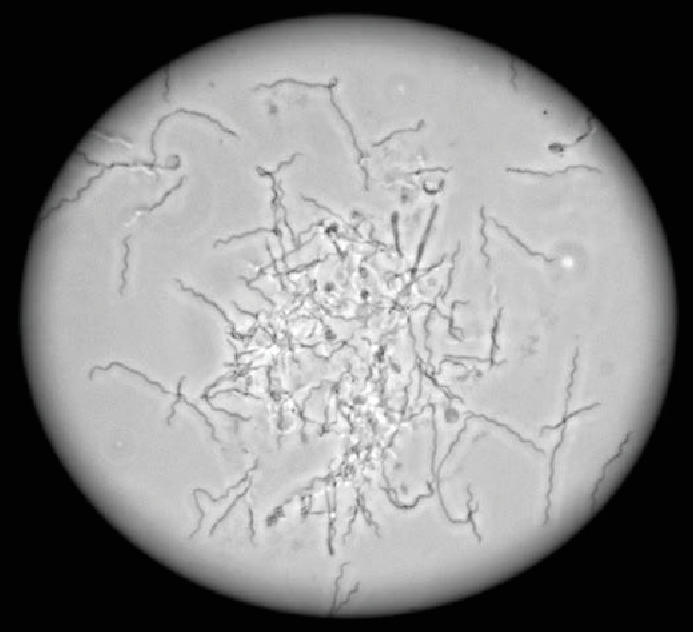

Příčina digitální dermatitidy byla studována pomocí klasických mikrobiologických i molekulárně biologických metod. Tyto studie odhalily, že nejčastějšími mikroorganismy na povrchu kůže v meziprstním prostoru nebo v jejich hlubších vrstvách jsou druhy Treponema. Treponemy (spirochety) nejsou pouze bovinní patogeny. Některé druhy způsobují také syfilis a onemocnění dásní u lidí. Treponemy jsou velmi tenké (desetkrát tenčí než lidský vlas), spirálové (spirochety) a pohyblivé anaerobní bakterie, které jsou schopné tvořit v nevhodných podmínkách cysty ("spóry"). Tyto bakterie rostou velmi pomalu a jsou velmi citlivými organismy. I v laboratorních podmínkách lze viditelného růstu dosáhnout až po 7 dnech. Kromě toho lze optimálního pomnožení dosáhnout v úzkém rozmezí, pokud jde o pH, teplotu, požadavky na živiny a koncentraci kyslíku. Všechny tyto příznivé podmínky lze nalézt ve výkalech a v kejdě, kde se treponemy množí. Hnůj a kejda jsou hlavní zdroje infekce paznehtů, způsobené bakteriemi treponema.

Treponema spp. pod mikroskopem (zvětšení 40X